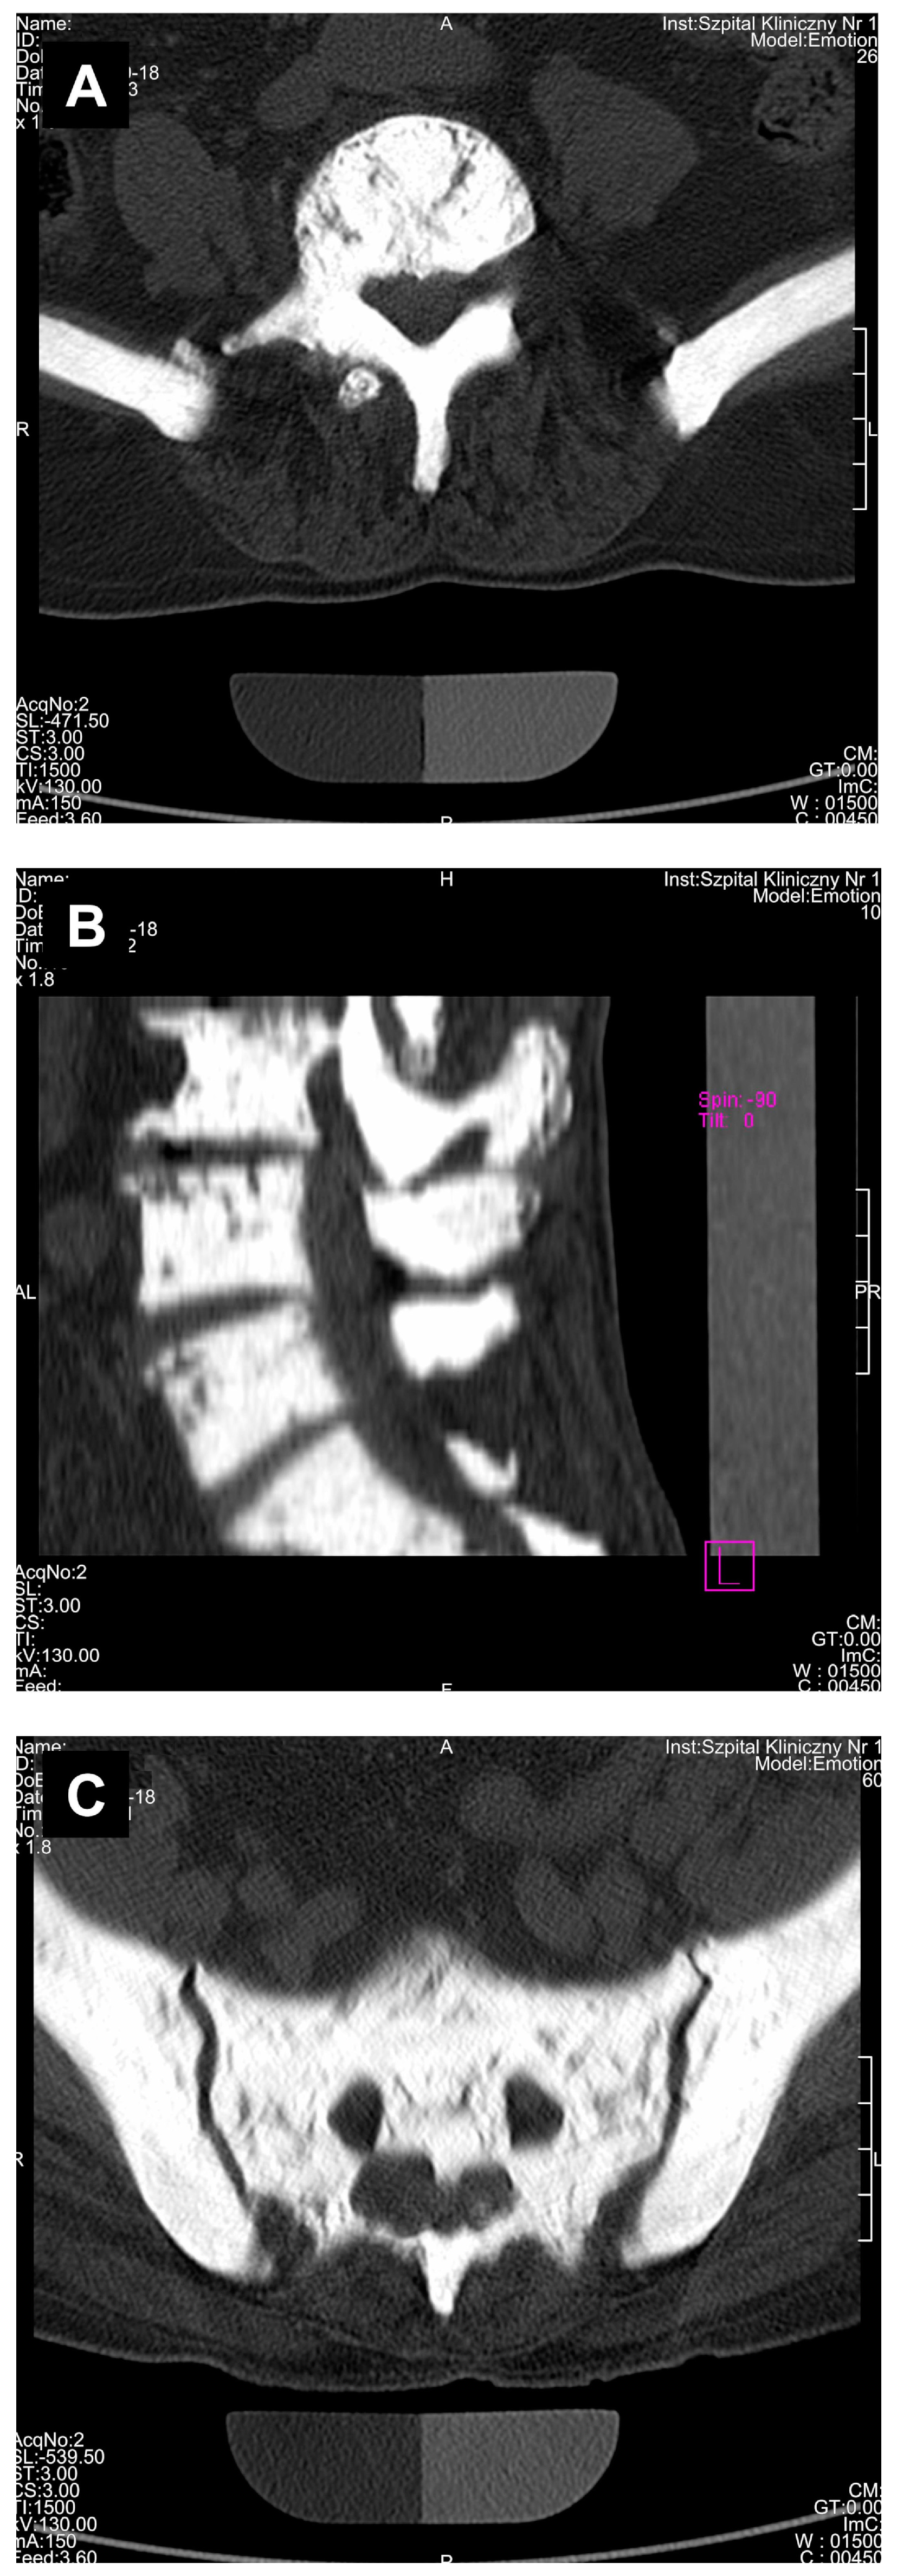

3. Results